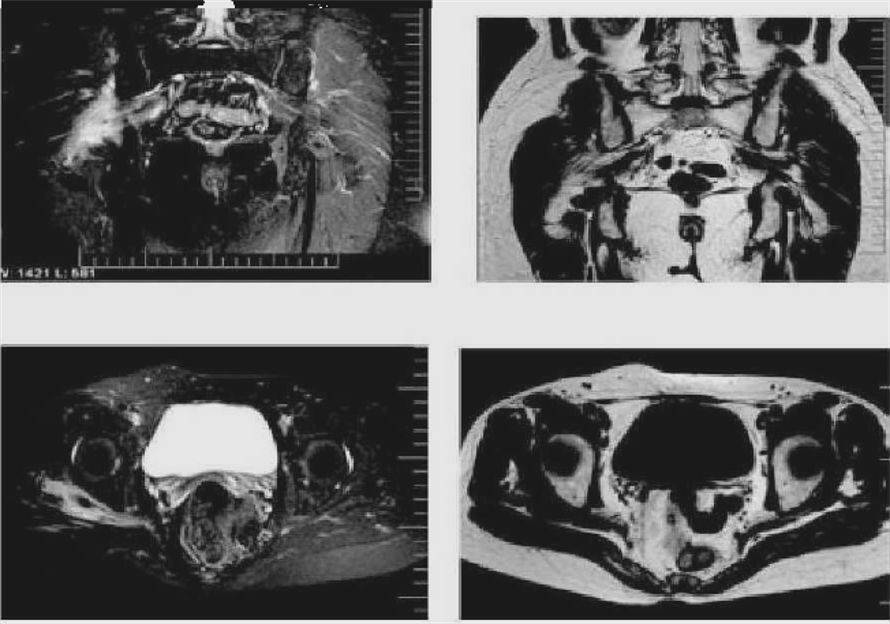

图谱--梨状肌综合征相关mri

图谱——梨状肌综合征相关mri,纯干货!